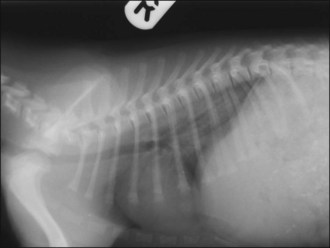

Respiratory distress: brain injury can give rise to neurogenic (non-cardiogenic) pulmonary oedema that usually develops within minutes to a few hours of the event. Thoracic radiographs typically show a caudodorsal distribution of lung field changes consistent with pulmonary oedema (interstitial to alveolar pattern) (Figure 28.1). Treatment involves oxygen supplementation and minimal stress; neurogenic pulmonary oedema is likely to be of mixed cause and a single low dose of furosemide may be rational. Clinical improvement is typically noted within 24–48 hours.

image

Figure 28.1 Thoracic radiograph of a puppy with head trauma showing caudodorsal lung changes consistent with neurogenic (noncardiogenic) oedema.